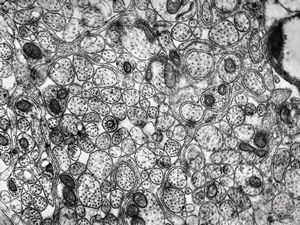

F,50y. | progressive multifocal leukoencephalopathy- viral particles in a glial cell

F,50y. | progressive multifocal leukoencephalopathy- viral particles in a glial cell

F,50y. | progressive multifocal leukoencephalopathy- viral particles in a glial cell